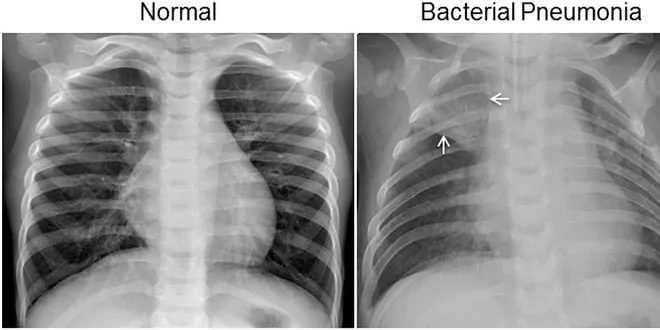

Google’s AutoML vs. a Hand-Made Model in Identifying Pneumonia

Towards Data Science

There has been a lot of talk recently about the potential for AutoML or “driverless ML” to change the way that machine learning is done and put the technology in the hands of non-coders. Google is…

📚 Read more at Towards Data Science